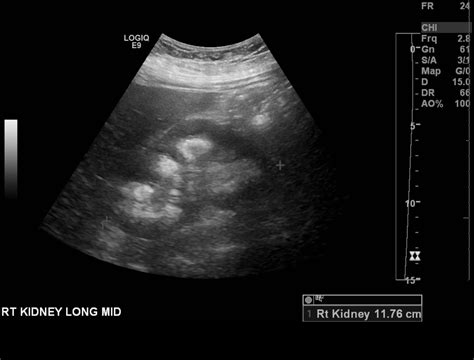

Chronic kidney disease can also affect the function of the kidney medulla, leading to progressive loss of renal function. This condition is characterized by the gradual destruction of renal tissue, including the medulla, resulting in the loss of the kidney's ability to concentrate urine and maintain electrolyte balance. Chronic kidney disease requires long-term management to slow the progression of the disease and prevent complications.